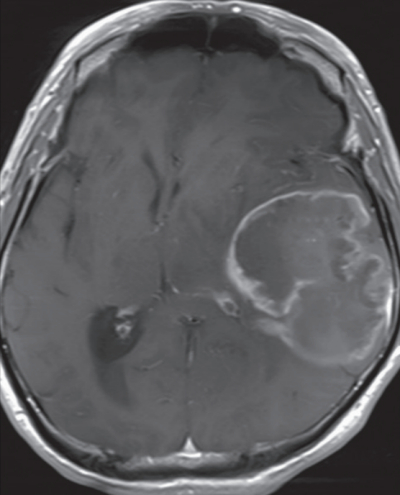

52 歳の男性。右片麻痺を主訴に来院した。1 か月前から早朝に激しい頭痛を自覚していたが、市販の鎮痛薬を内服して様子をみていた。10 日前から右上下肢の脱力が出現し、次第に増悪したため受診した。既往歴に特記すべきことはない。

身長 172 cm、体重 68 kg。体温 36.2 ℃。脈拍 72/分、整。血圧 134/82 mmHg。呼吸数 16/分。右利き。徒手筋力テストで右上下肢共に 3 の片麻痺を認める。頭部造影MRI の T1 強調水平断像と冠状断像を別に示す。翌日、開頭腫瘍摘出術を行うこととなった。